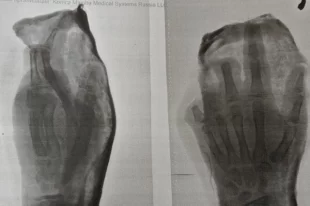

Детям оторвало пальцы при взрыве петарды в Северной Осетии

Одному из пострадавших проведена ампутация III, IV и V пальцев левой кисти.